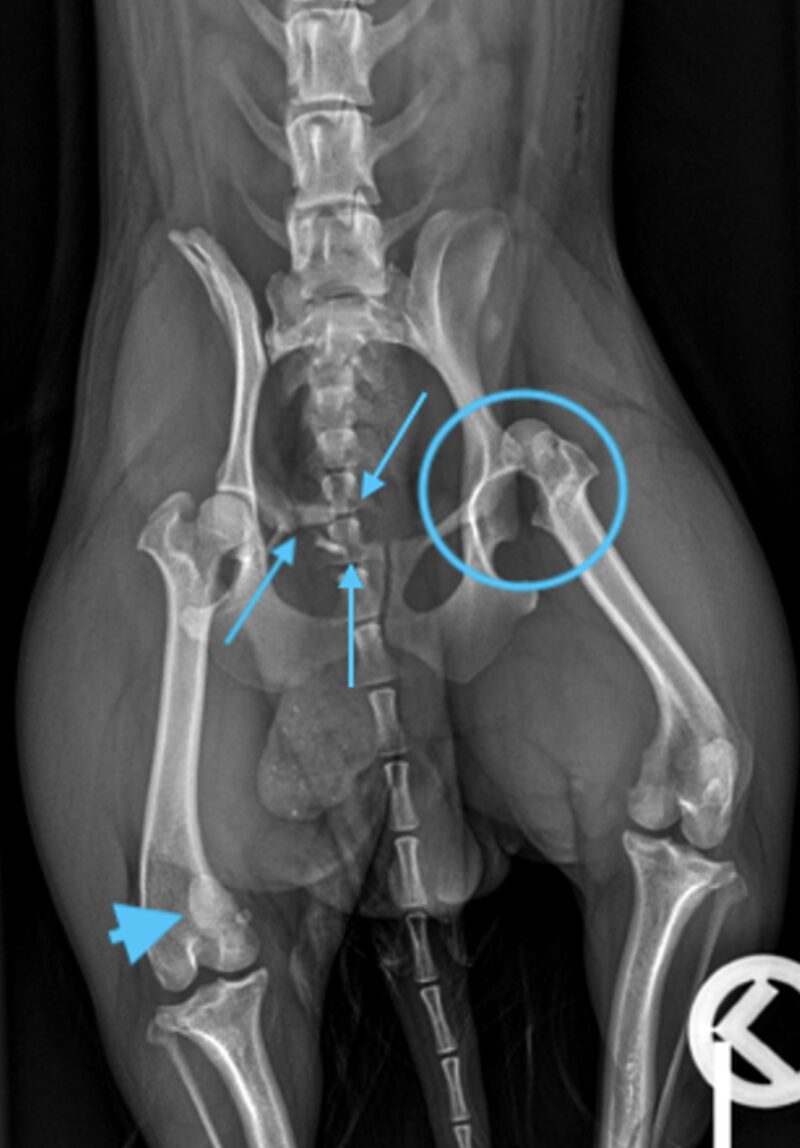

Auf der lateralen und ventrodorsalen Aufnahme des Beckens ist eine segmentale Fraktur des rechten Os pubis erkennbar. Es sind drei Frakturstellen identifizierbar (blaue Pfeile), eine zwischen Corpus ossis pubis und Ramus cranialis, die möglicherweise unvollständig ist. Eine weitere Fraktur im Ramus cranialis ossis pubis und die letzte zwischen Ramus cranialis und Ramus caudalis ossis pubis. Aus dieser Fraktur entstehen zwei Fragmente, von denen eines nahe dem Corpus ossis pubis liegt und geringgradig nach kranial verschoben ist, während das andere frei in den Weichteilen liegt und zwischen den beiden Frakturen zentriert ist. Die Konturen der Frakturen sind alle scharf abgegrenzt, was auf ein akutes Trauma hinweist. Die Symphisis pubis scheint leicht nach links lateral verschoben zu sein. Um eine Verschiebung des Beckens zu ermöglichen, sind drei orthogonale Frakturen erforderlich, die auf diesen Röntgenbildern nicht erkennbar sind.

Der rechte Femurkopf ist vollständig aus dem Acetabulum luxiert und nach kranial und dorsal verschoben (blaue Kreise). Die Weichteile des linken Femurs sind geringgradig verdickt. Im linken lateralen Aspekt der abdominalen Wand ist eine minimale Luftansammlung erkennbar. Beidseits sind die Coxofemoralgelenke geringgradig nach außen rotiert, welches eine laterale Positionierung der Patellae verursacht. Im rechten Kniegelenk befindet sich die Patella jedoch in medialer Position (blauer Pfeilkopf). Es ist unklar, ob ob diese traumatisch oder rasse-bedingt entstanden ist und welcher Grad der Patellaluxation vorliegt. Die sichtbaren caudalen abdominalen Organe sind ohne besonderen Befund.

Es handelt sich um eine akute, geschlossene, monostotische, segmentale Fraktur des rechten Os pubis, eine kraniodorsale Luxation des linken Femurs, eine mediale Luxation der rechten Patella und eine geringgradige Weichteilschwellung des linken Oberschenkels.

Es handelt sich um eine akute, geschlossene, monostotische, segmentale Fraktur des rechten Os pubis, eine kraniodorsale Luxation des linken Femurs, eine mediale Luxation der rechten Patella und eine geringgradige Weichteilschwellung des linken Oberschenkels."